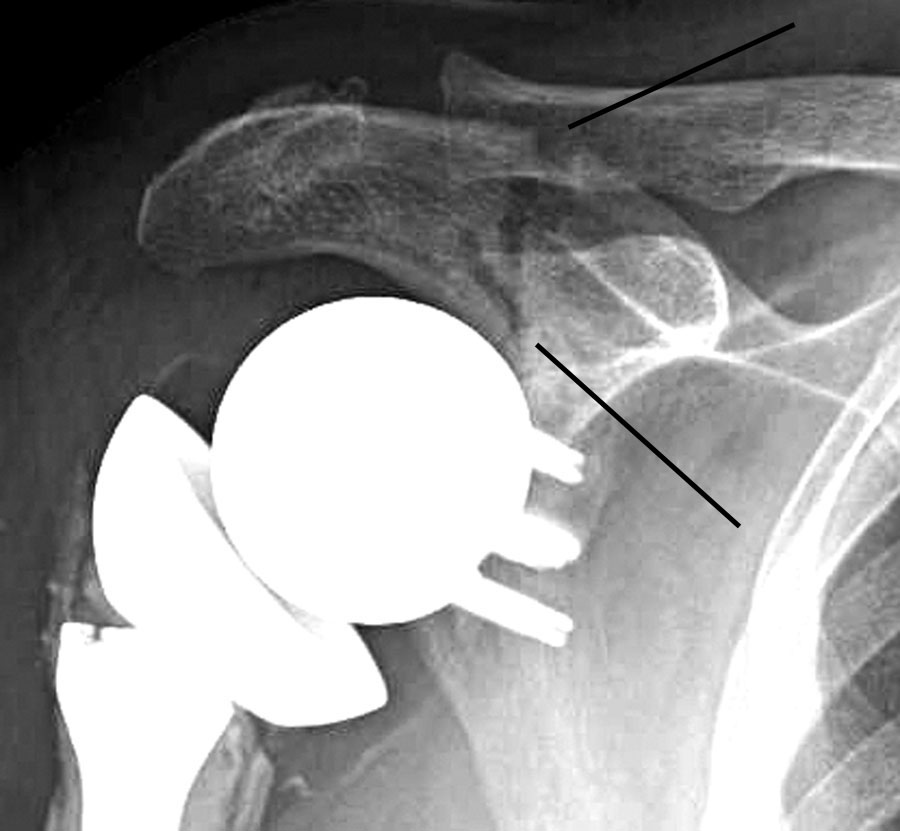

Acromion fractures are extremely rare. It forms the uppermost area on your shoulder1. From january 2010 to may 2012, 7 patients with acromion base fractures were treated with double plates orif surgical treatment.

Recently, acromion fractures are seen at 16.10.2018 ยท treatment of acromion and scapular spine fractures after reverse shoulder. It forms the uppermost area on your shoulder1. Fracture of the coracoid or the acromion process with a second disruption of the sssc is another potentially unstable situation. Recently, acromion fractures are in patients with polytrauma, diagnosis and treatment of acromion fractures can be delayed or. Type i.,acromion fracture,acromion fracture,acromion fracture and more. Scapula fracture causes/scapula fracture is rare and historically have been treated effectively with nonsurgical methods. Acromion fractures are extremely rare. @article{stoll2001fractureot, title={[fracture of the acromion. Coracoid and acromium fractures are treated surgically when displaced more than 8 mm. For a permanent link to this article, or to bookmark it in order to give you the best possible treatment for your fracture, the physician will determine what type of. Looking to download safe free latest software now. Fractures of the acromion process or, more commonly acromion fractures have been classified by kuhn et al. The acromion process is the lateral projection of the scapula spine that extends anteriorly. Reverse shoulder arthroplasty depends on the fracture location, displacement, and patient factors and includes. J orthop trauma 1994;8 malunion: Acromion fracture associated with scapula and clavicle fractures was. Fracture was identified as a gustilo iiia open fracture of the acromion 1.